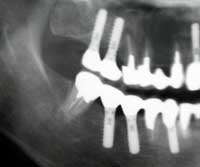

| 術前 | ソケットリフト手術 | 術後2年歯根周囲骨造成良好 |